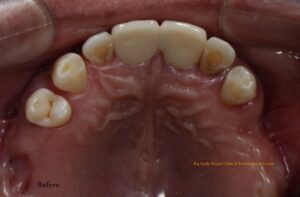

A 50-year-old male patient from New Zealand arrived at our clinic seeking to replace his upper teeth. He had recently returned to Nepal for a 20-day visit and had already explored treatment options at other dental facilities. Unsatisfied with both the proposed treatment plans and the costs, he came to us with his desires and expectations. We listened attentively, taking careful note of his needs. He had already had X-rays taken at the request of a previous dentist.

On his first visit, we performed a thorough examination of his teeth and gums. He had upper back teeth missing and remaining upper front teeth were mobile, whereas his lower teeth were not mobile but required gums treatment. We explained his condition of oral hygiene and treatment required. We presented him with all available options, including removable and fixed prostheses. He opted for a fixed prosthesis with upper arch replacement using 4 dental implants (All-on-4). We also discussed different implant brands and types, and he selected Bredent Copasky implants (Fast & Fixed). Additionally, we offered various prosthetic options for permanent prosthesis, and he chose a hybrid denture.

Fig: Pre-operative extra-oral, intra-oral photographs and X-ray